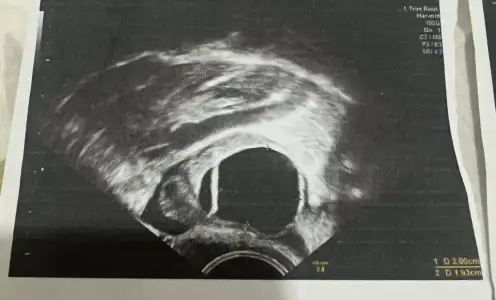

kızlar yumurtam her ay genelde kist yapıyor bu ay artık bu sorun üzerine doktora gittim bir kaç vitamin kullanıyorum, doktor ya çatlamış ya çatlamak üzere dedi net anlamadım chatgpt de kenarları düzgün çatlamamış görünüyor dedi kafam karıştı anlayan varsa bakabilir mi ? çatlama sonrası olan sıvı gözüküyor mu?

Aşko bak şimdi yumurta çatlamamışsa böyle büyük içi dolu kesecik gibi görünür senin ultrason resmi gibi. Patlamış yani çatlamış olan folikül yumurta küçülür sıvısını bırakır döllenmeye hazır bekler diye biliyorum ben aklımda kalmış daha önce yumurta takibi yaptırırken doktorum demişti, yumurtan çatlamış bekliyor demişti hatta büzüşmüş demişti çatlarken küçülüyor onlar

benim doktor perşembe günü 17 mm dedi cumartesi gittim 20 21 mm büyük ihtimalle çatlamış dedi sıvıdan falan bahsetti, zaten ağrıyı bugün hissettim yanma oldu sağ tarafta acaba çatlamadı kiste mi dönüştü dedim. yani sizin dediğiniz gibi hala 20 mm olup küçülmediyse çatlamamış demek oluyor